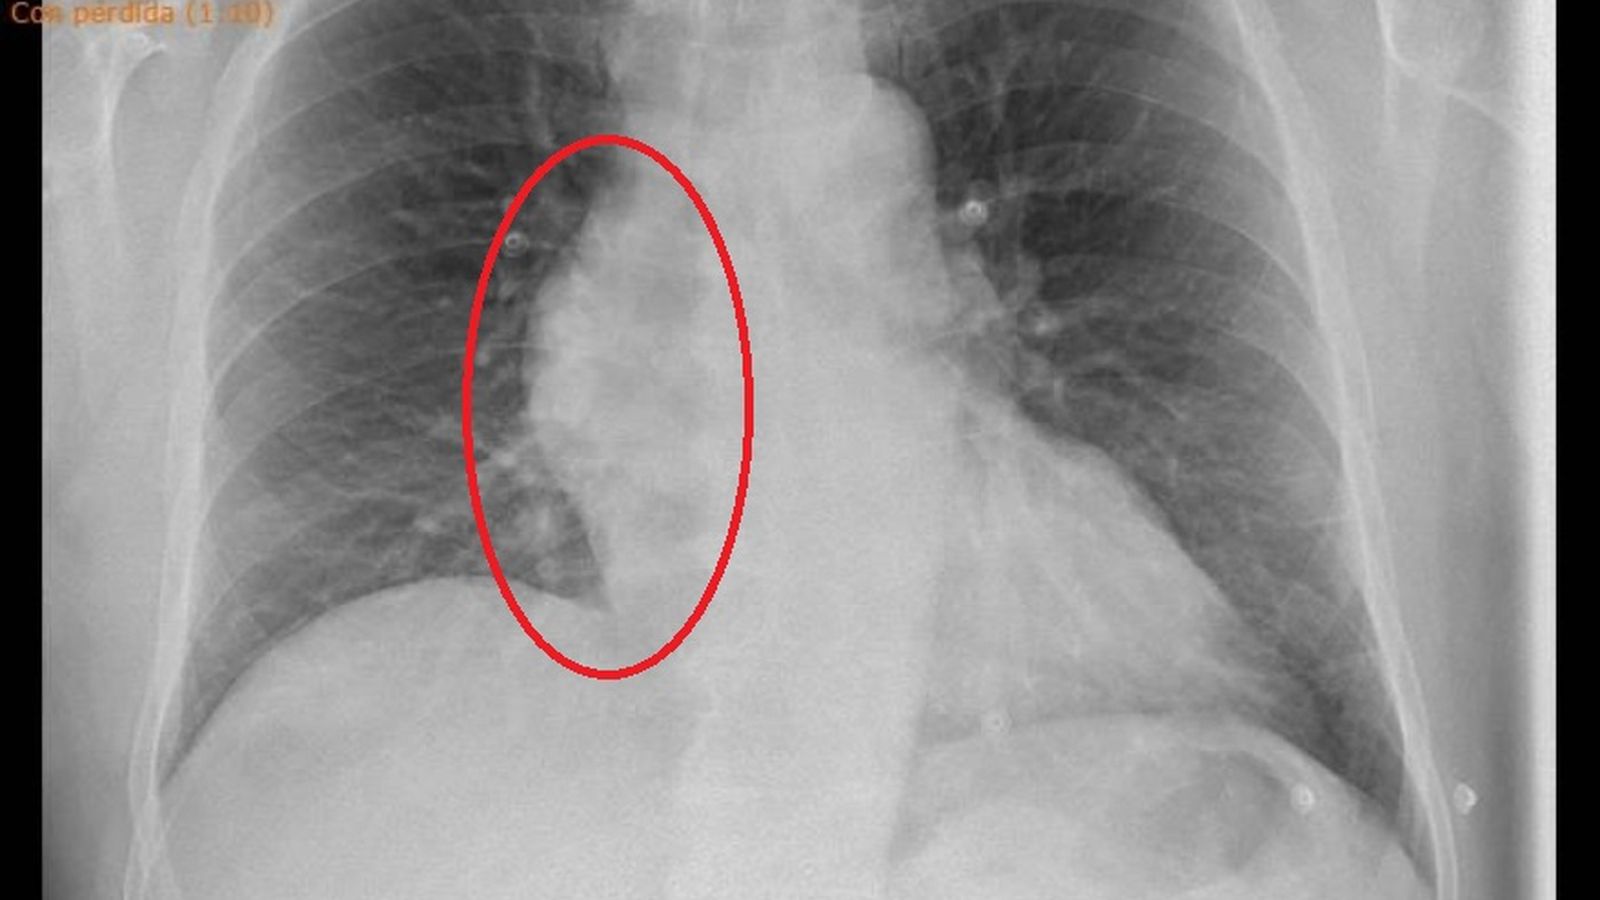

Según expone la familia en su reclamación, a pesar de que la radiografía de tórax "mostraba claramente un marcado ensanchamiento mediastínico, con un evidente aumento de tamaño de la silueta de la aorta ascendente, muy sugestivo de dilatación patológica aórtica, fue dado de alta a las 16:48 horas con el diagnóstico de "GEA" (gastroenteritis aguda), con tratamiento analgésico. El paciente continuó en todo momento con el dolor abdominal, sin que en ningún momento se acompañara el dolor de vómitos ni diarrea.

Esta radiografía, a la que ha tenido acceso este periódico, no se reseña en el informe de alta de Urgencias.

La radiografía de tórax del paciente que muestra un marcado ensanchamiento mediastínico, según explica la reclamación presentada por la familia.

La radiografía de tórax del paciente que muestra un marcado ensanchamiento mediastínico, según explica la reclamación presentada por la familia. / M. G.

“Las deficiencias en la atención médica impidieron el diagnóstico y, consecuentemente, que el paciente tuviera la oportunidad de recibir tratamiento primero médico y luego quirúrgico urgente, que eran vitales para que pudiera sobrevivir”, concluye Pedro Arnaiz, pues “hubo un fallo en la valoración radiológica de la Radiografía de tórax con ensanchamiento mediastínico por dilatación aórtica. La combinación de este hallazgo con un dolor tóraco-abdominal con sensación de pérdida de consciencia inminente, era altamente sugestiva de disección aórtica”, subraya el experto.

El letrado concluye que “la correcta valoración de la radiografía de tórax, junto al dolor abdominal intenso con leucocitosis y con neutrofilia y la sensación de pérdida de conciencia inminente, obligaba a observar al paciente estrechamente, buscando identificar la causa subyacente de manera urgente, cosa que no se hizo en este enfermo, a quien se envió a su casa con el diagnóstico erróneo de un proceso leve, como es una gastroenteritis aguda, abocándole a la muerte, pues si se hubiese indicado una Angio-TAC, hubiera llevado a cirugía urgente que habría permitido como en la inmensa mayoría de los casos la rotura de la arteria, la insuficiencia aórtica aguda y la muerte por taponamiento cardiaco”, por lo que el paciente “fue privado del único tratamiento capaz de evitar el desenlace fatal como consecuencia del taponamiento cardiaco por rotura aórtica”.

Según la reclamación presentada ahora al SAS, “esta actuación de quien dio de alta a este paciente en el servicio de Urgencias del Hospital Macarena, sin valorar una radiografía de tórax altamente patológica, pues presentaba un marcado ensanchamiento mediastínico, con aumento de tamaño de la silueta de la aorta ascendente, altamente sugestivo de patología aórtica, desatendiendo además los signos clínicos y analíticos de gravedad que mostraba al dar de alta con un diagnóstico trivial (gastroenteritis aguda), fue gravemente negligente, pues se omitieron los protocolos diagnósticos y terapéuticos obligatorios ante una patología con alta sospecha de riesgo vital".